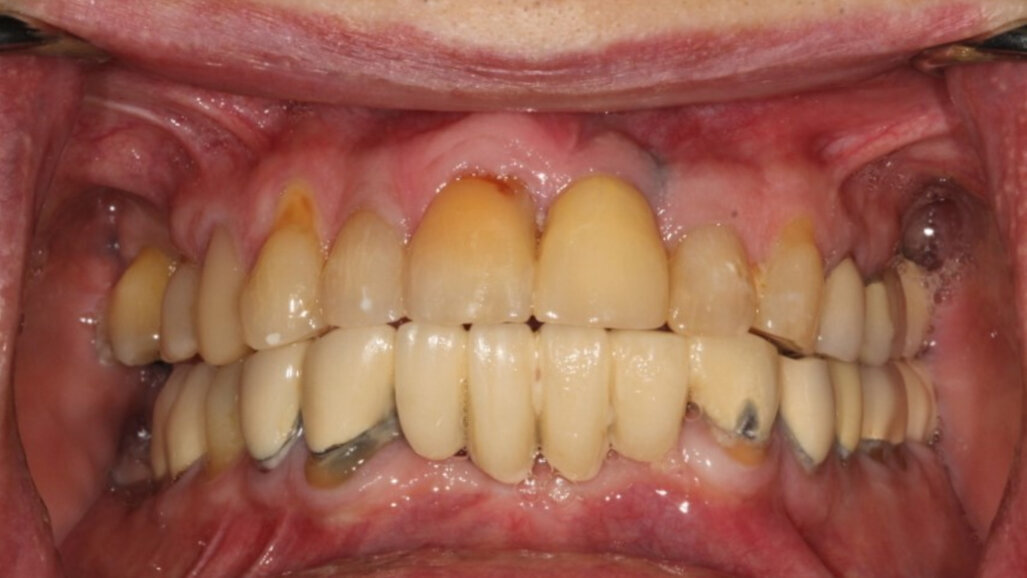

Fig. 1: Failing mandibular dentition. (All images: Daniel Madden)

The patient presented with multiple periapical radiolucencies associated with failing endodontically treated teeth, a horizontal root fracture and a failing long-span bridge (Fig. 1). A poor long-term prognosis was given to all the remaining mandibular teeth except tooth #46 (Fig. 2), and the treatment options, limitations and risks were reviewed thoroughly with the patient. The patient did not want a removable restoration and did not want to go a day without teeth and wanted to have biologically friendly materials used for treatment. It was decided to perform an immediate implant surgery and provide the patient with a stable temporary restoration to protect the healing implants for long-term success.